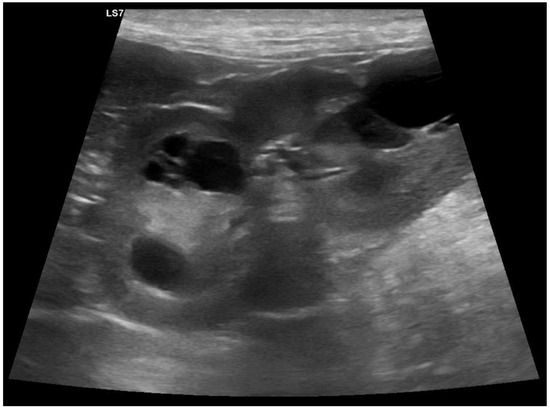

3.1. Clinical Phenotype